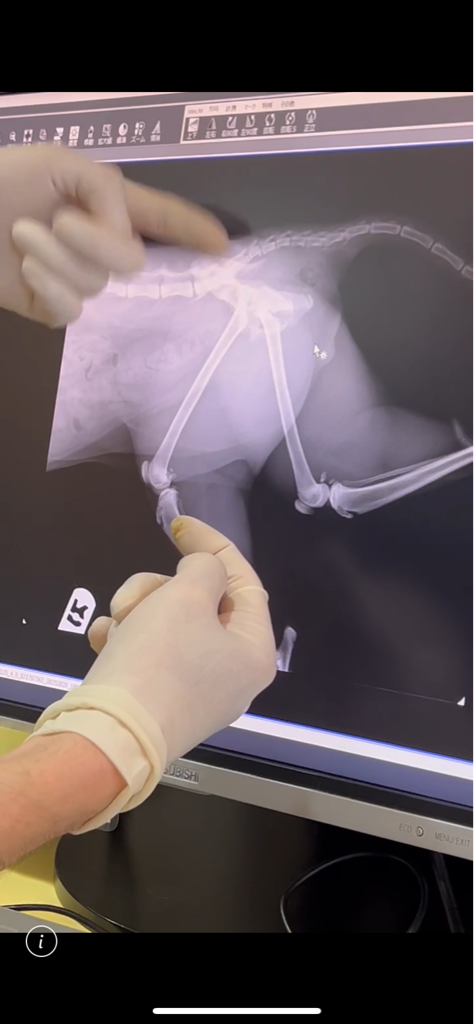

やはり 骨折ですね。。。

骨折して完全にズレています

今後 チャト君の様に排便、

排尿障害が出なければ良いのですが、

日曜日には手術になる予定です。